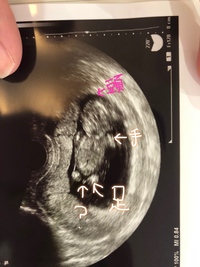

12週の時の様子です。立体的ですよね! Photo by It Mama こちらは1人目の時の3Dエコーの画像。手と横顔の様子がはっきりわかりますね。 3Dや4Dに対応した超音波診断装置を導入している産院も増えています。 妊娠12週~16週になると、お腹の赤ちゃんが大きくなり過ぎて、経膣エコーでは撮影が難しくなります。 女の子の場合は、足の間に突起物がなく、三本線で木の葉のようなマーク"女の子のシンボル"が見えれば判別されます。 2d、3d、4dエコーには 25週5日(25w5d・女の子)|ナオミン さん(24歳) エコー写真撮影時のエピソード: この子は2人目の女の子のエコーです。 1人目は男の子で、年子です。 エコーで見ているとき、カメラ目線で「やっほー」ってやっているみたいでかわいかったです。26週6日(26w6d・女の子)|

12週 :この段階では、 約7%のナブが不確定であり 、 「どちらの可能性もある」範囲内 である。 13週 :この時点で、男の子のナブと女の子のナブはまだ同じサイズですが、実際の生殖器になるために成長しています。 それでもナブの6%はまだ不確定 で 妊娠9週頃から区別がではじめ、妊娠12週頃には外性器が形成されます。 しかし16週頃の赤ちゃんには、男の子でも女の子でも突起物の様なものが見える事が多いと言います。 下の子は女の子でしたが、19週で4dで診てもらった時、先生に「女の子だね! 16週2日(16w2d・性別不明)|みみみさお さん(26歳) エコー写真撮影時のエピソード: 現在妊娠17週2日のプレママです。 妊娠12週あたりから手の公にぷつぷつとした乾燥湿疹のような湿疹ができはじめて、オリーブオイルと椿オイルで保湿していました。 妊娠12週目の赤ちゃん